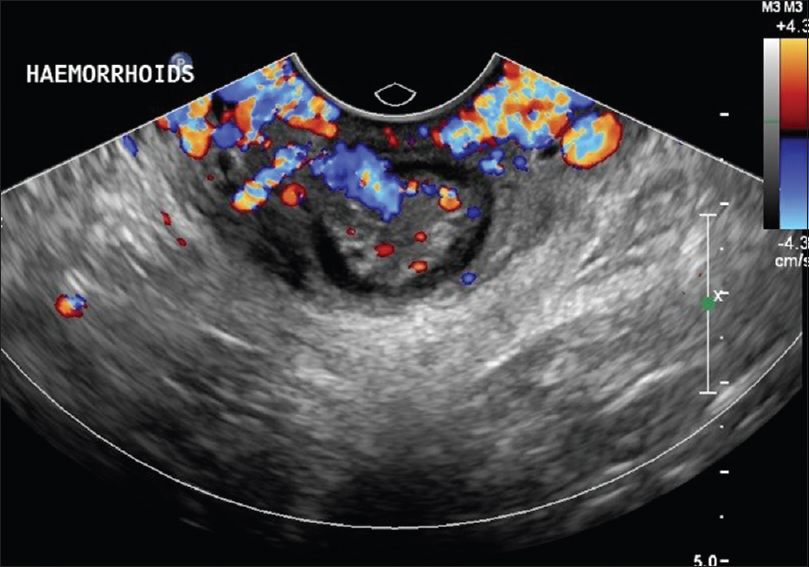

- Перианал. Установите датчик в том же положении, что и выше, под углом кзади к анальному каналу. Варикозное расширение будет видно дистальнее анального кольца, и геморрой, если он присутствует, может распространиться в анальный канал [Рисунок 24] .

Рисунок 24: Анальное кольцо с рефлюксным варикозным расширением вен Вальсальвы